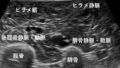

Write vs Read Zoom 実際の画像で比較

今回も私の肝臓画像で比べてみました。

使用機器は富士フイルムのARIETTA750です。こちらの機種ではWrite Zoom→Hi Zoom、Read Zoom→PAN Zoomと記載されています。

まずは通常のBモード画像。

次はWrite Zoomで記録した画像です。

おお、走査線数が増えているから全くぼやけないですね。

続いてRead Zoomです。

じゅうぶんキレイな画像ですが、Write Zoomに比べると少し柔らかさを感じます。

ふたつの画像を並べてみます。

左がWrite Zoom、右がRead Zoomです。こうやって比べてみると違いが分かりますね。